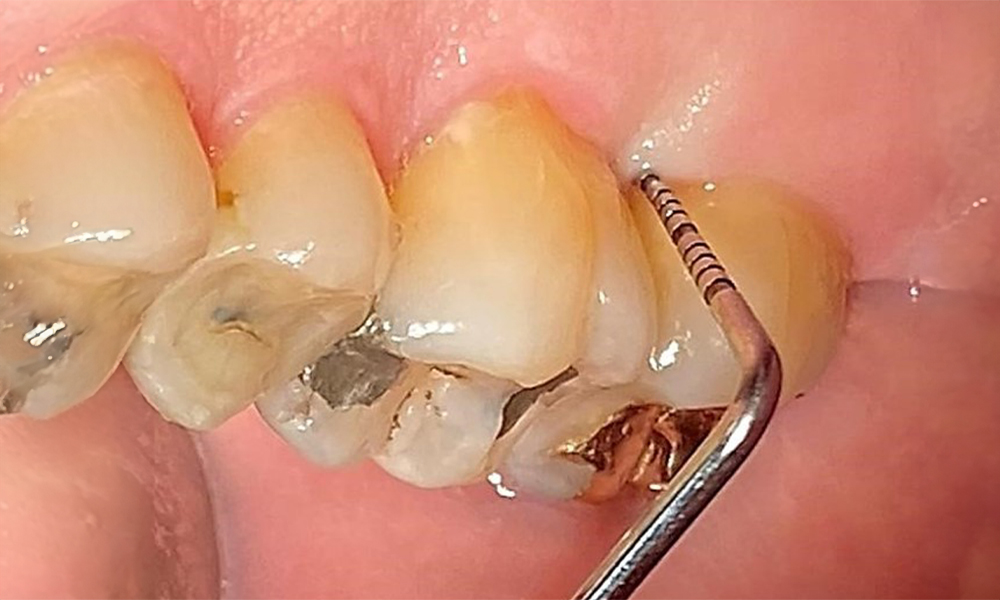

Okklusalansicht Oberkiefer. Insuffiziente Amalgamfüllung 14 mit Randspalt. © Dr. R. Krapf

Abb. 5 Okklusalansicht Oberkiefer. Insuffiziente Amalgamfüllung 14 mit Randspalt. © Dr. R. Krapf

Der Patient hat ein vollbezahntes Gebiss mit 28 Zähnen, an welchen sich im Molaren- und Prämolarenbereich Amalgamfüllungen und Compositefüllungen befinden. An Zahn 14 zeigt sich ein sichtbarer klinischer Randspalt. Zahn 27 hat ein suffizientes Goldinlay. Zudem zeigen sich generalisierte Attritionen und Abrasionen. (Abb. 2, Abb. 3, Abb. 4, Abb. 5, Abb. 6)